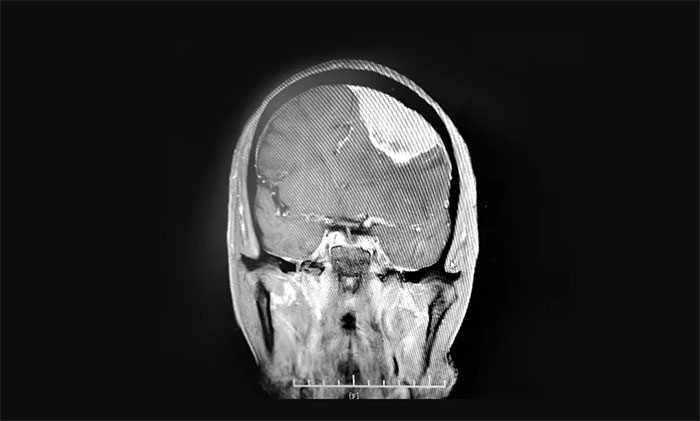

入院檢查,頭顱MRI提示:左側(cè)額葉大腦凸面可見巨大團(tuán)塊狀異常信號(hào),周圍可見明顯水腫信號(hào),胼胝體明顯腫脹,臨近左側(cè)腦室受壓向右側(cè)移位,中線結(jié)構(gòu)輕度右移,病灶大小約7.2×3.3×3.2cm。

▲ 腫瘤位于左側(cè)額部